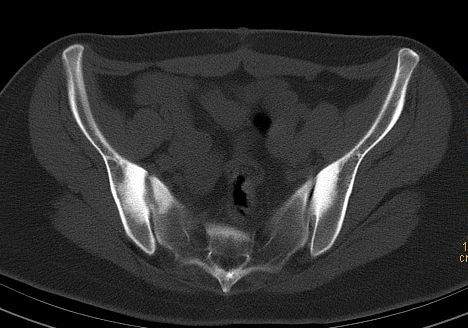

髂骨致密性骨炎 (osteitis condensans ilii)

髂骨致密性骨炎 (浏览次数:约 1428 次,好评数: 2个)